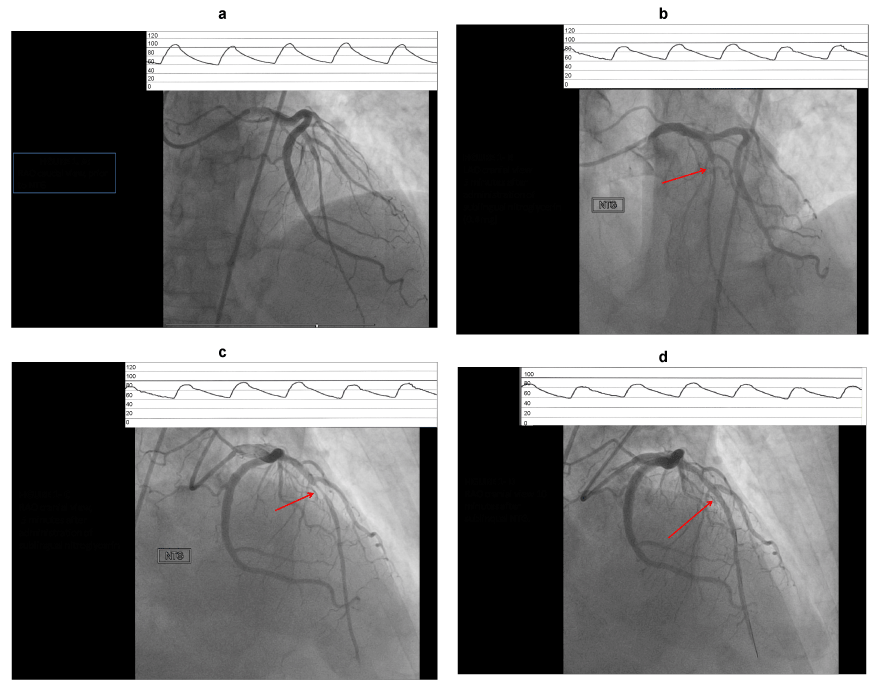

| Figure 1: Coronary angiogram RAO and LAO views showing moderate disease of mid LAD (a), severe narrowing of the segment 5 minutes after sublingual NTG administration (b & c) and resolution of severe narrowing 10 minutes after s/l NTG at the time when wire was introduced into the left anterior descending artery for IVUS evaluation. (Aortic pressure (mm Hg) tracings at the time displayed at the top). |